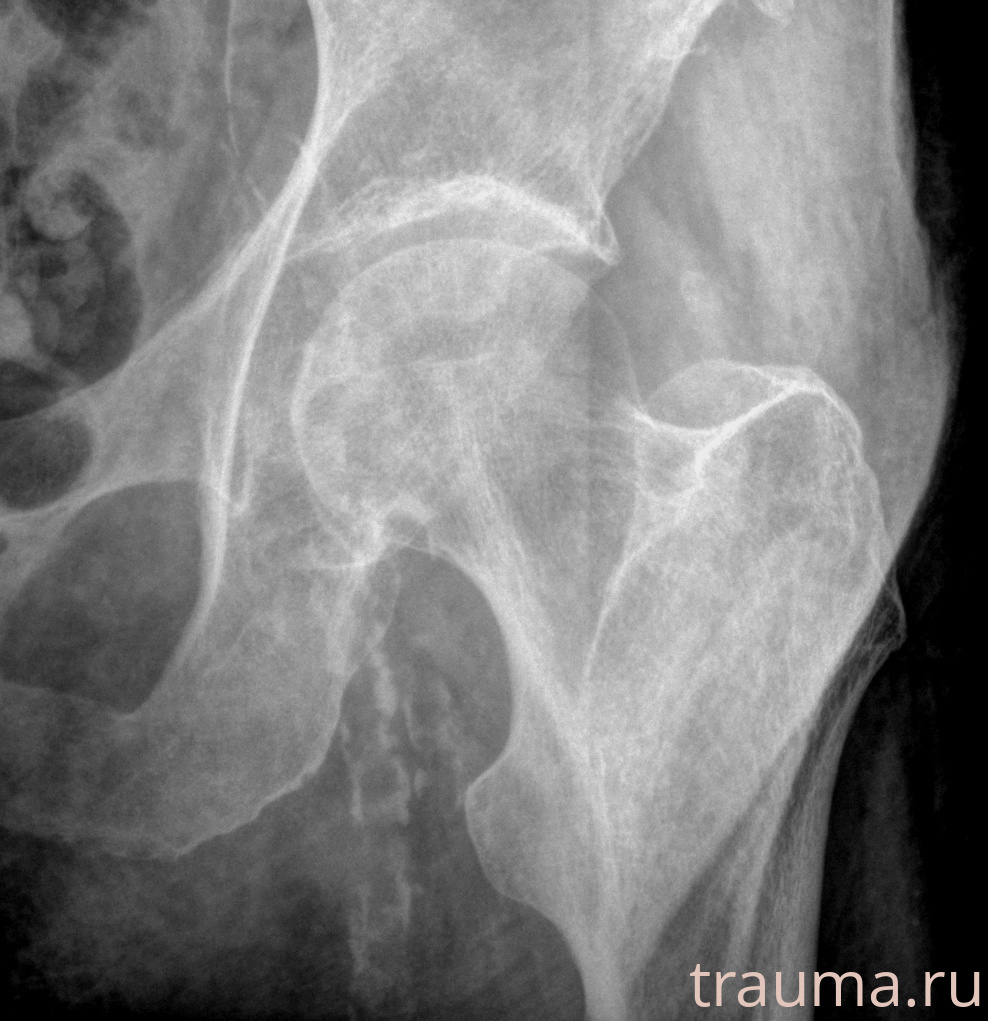

Рентгенограммы

Рентген на дому: по вашему адресу приезжает врач-рентгенолог, травматолог-ортопед с мобильным рентгеновским аппаратом, проводит диагностику травмы или заболевания, делает необходимые рентгенограммы, дает рекомендации по дальнейшему лечению. Получить качественные снимки в домашних условиях возможно благодаря уникальной методике, разработанной МосРентген Центром для института  Склифосовского